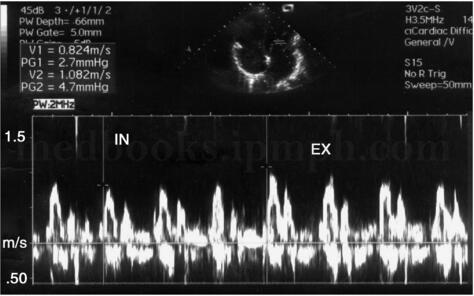

3﹒脉冲多普勒超声心动图 主要表现为左房室瓣口舒张早期前向血流速度明显增高、EF斜率快速下降、舒张晚期血流速度减慢,形成E峰高尖而A峰低小、E/A比值明显增大的图像,见图2‐1‐235。但此征象并不具有特异性,也可见于限制型心肌病或严重左房室瓣反流。缩窄性心包炎患者可出现呼气时二尖瓣E峰增高,吸气时下降,见图2‐1‐236;吸气时主动脉血流速度也明显减低,呼气时血流速度增快。

图2‐1‐236 缩窄性心包炎,呼气时二尖瓣血流频谱E峰 增高,吸气时下降(I N:吸气;EX:呼气)